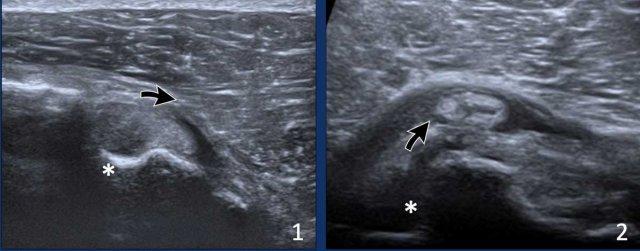

Images

- Vị trí lệch tâm của đầu dài gân cơ nhị đầu do lỏng lẻo của ròng rọc cơ nhị đầu.

- Trật khớp gân cơ nhị đầu. Lưu ý rãnh nhị đầu trống (dấu hoa thị)